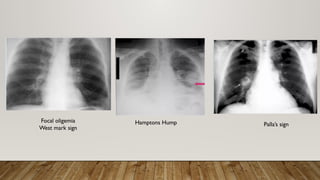

CHEST X-RAY

• Focal alveolar or interstitial infiltrate

• Pulmonary edema

• Bilateral cephalization of the pulmonary vasculature

• Peri-bronchial cuffing

• septal thickening,

• intralobular thickening

• widened mediastinum raises the possibility of a pericardial effusion.

Focal oligemia

West mark sign

Hamptons Hump Palla’s sign